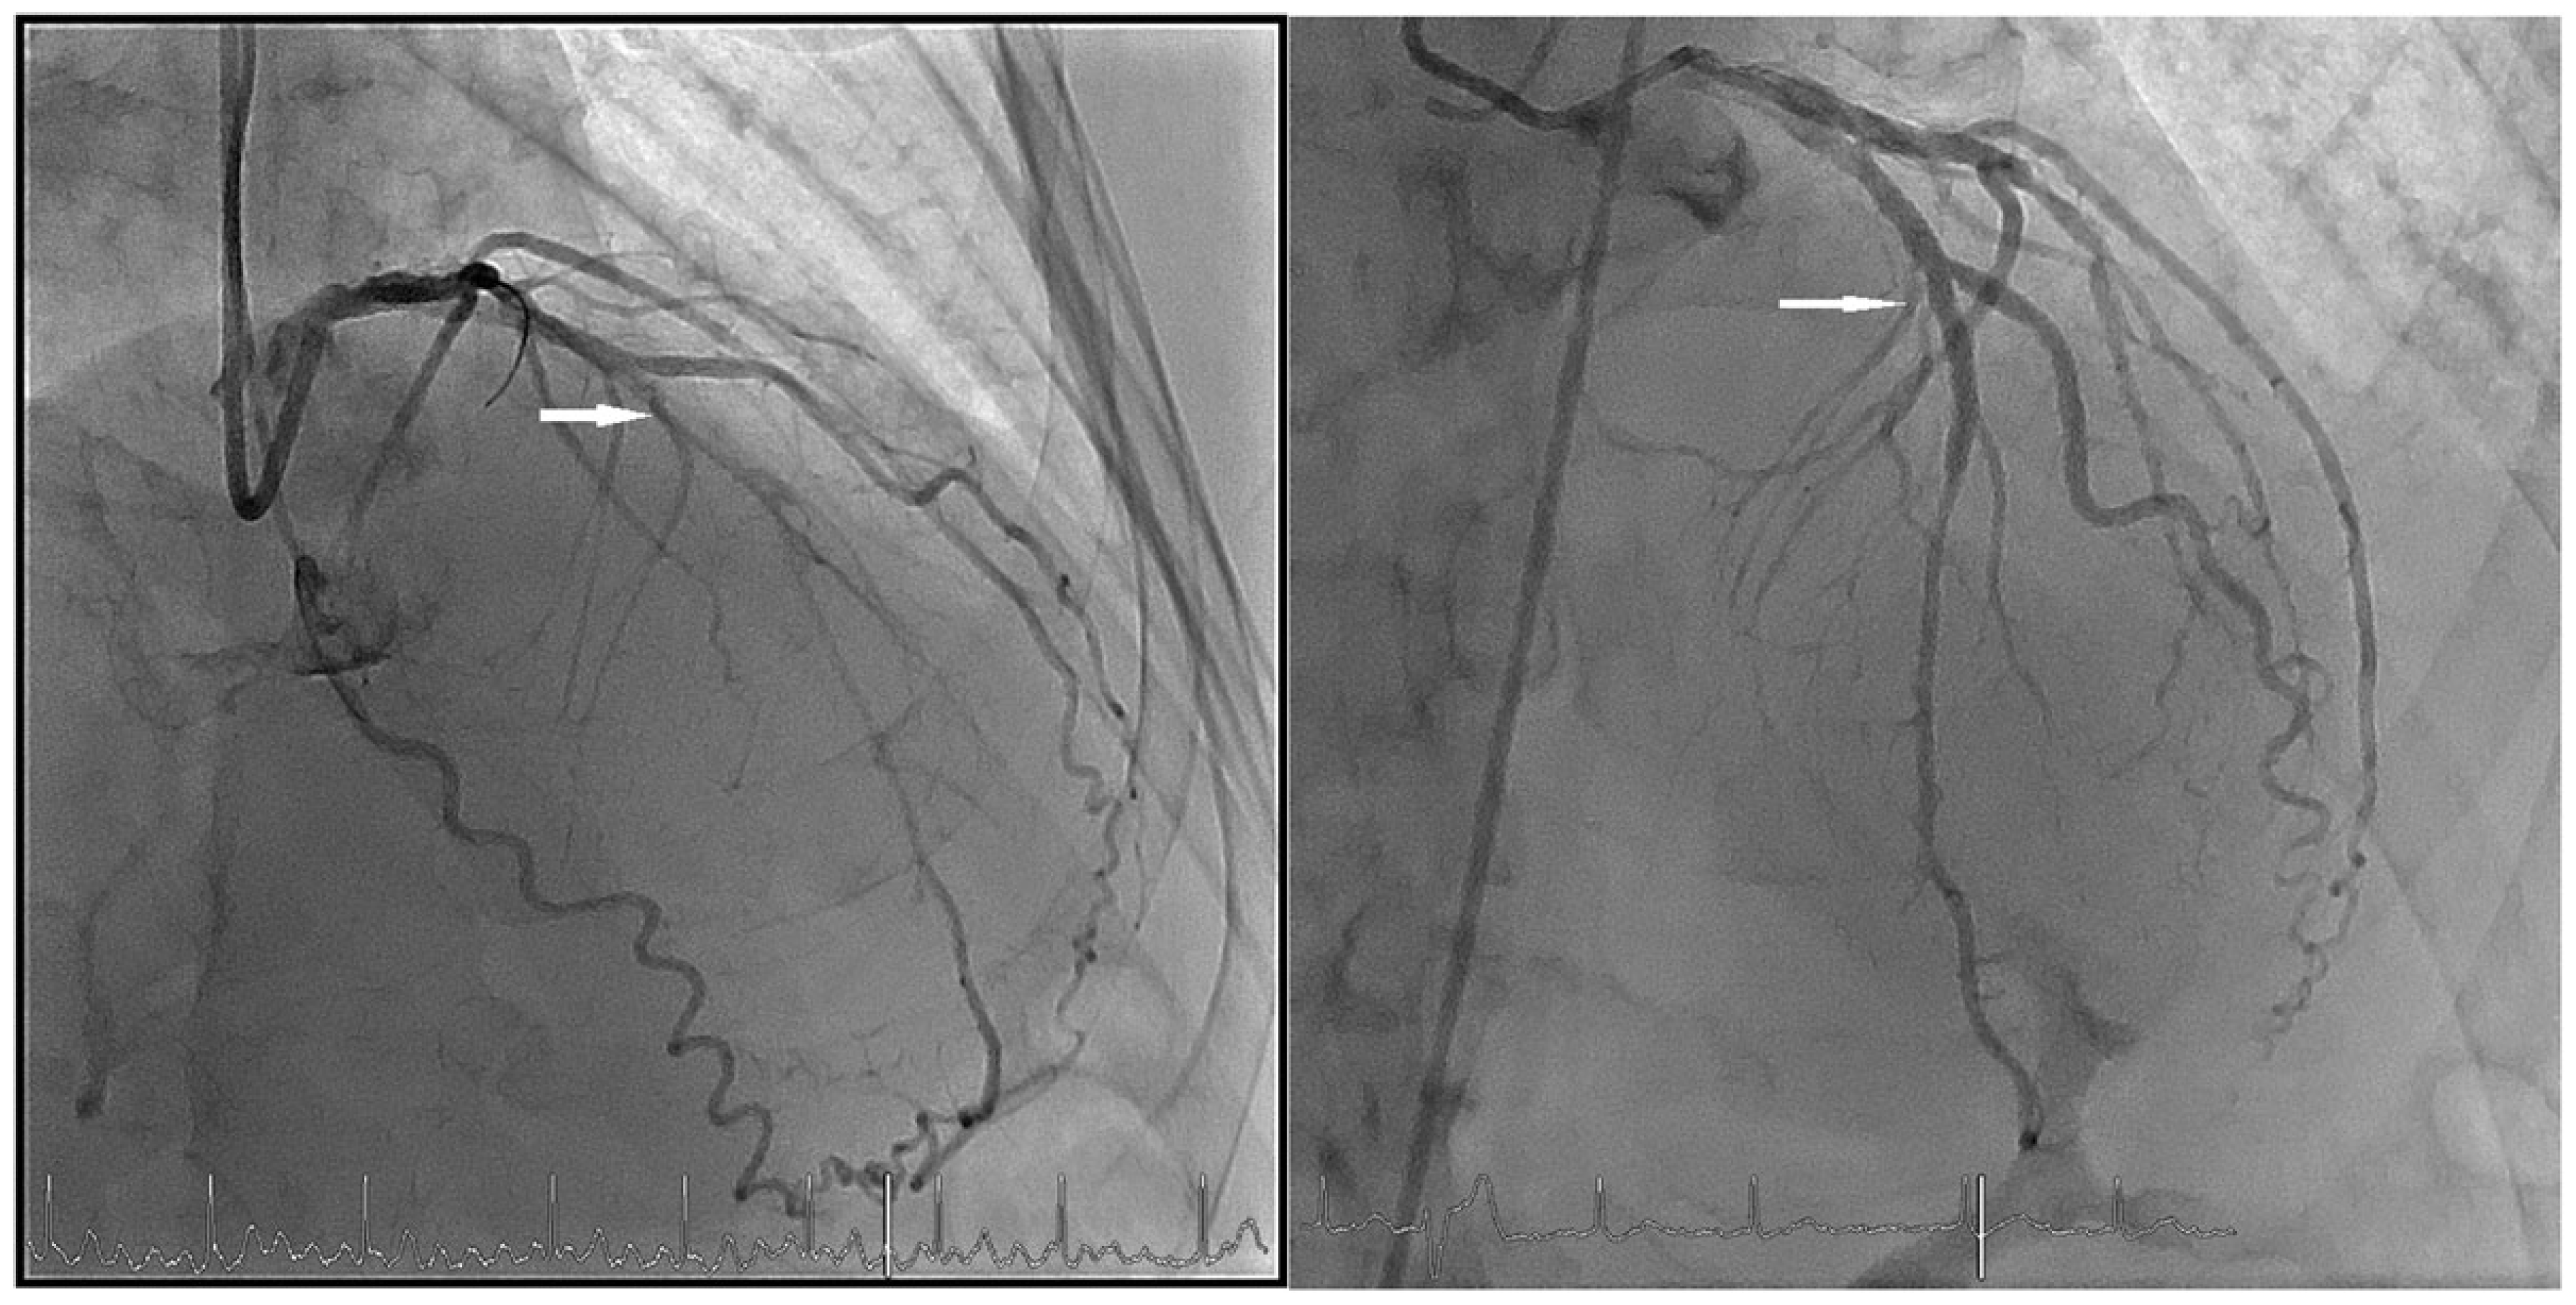

Case Report